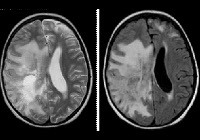

Электроэнцефалография показывает признаки диффузного поражения головного мозга: снижение альфа-активности и дезорганизация ритма; Эпилептиформная активность часто определяется. При исследовании спинномозговой жидкости было обнаружено увеличение уровня гамма-глобулина на фоне снижения удельного веса фракции альбумина. Наиболее информативным типом инструментальной диагностики является МРТ головного мозга. Болезнь Шильдера подтверждает наличие по крайней мере одного большого или пары слитых участков демиелинизации в белом веществе.

Многие неврологи используют критерии с.M. определить окончательный диагноз. Poser 1985: наличие по данным МРТ 1-2 круглых зон демиелинизации размером не менее 2х3 отсутствие надпочечниковой патологии; исключение любой другой патологии головного мозга (внутримозговая опухоль, диссеминированный энцефаломиелит, инсульт ); соблюдение нормы уровня жирных кислот в сыворотке крови; выявление в плотном срезе зон диффузного хронического рассеянного склероза. В некоторых случаях только гистологическое исследование тканей головного мозга пораженного участка позволяет отличить лейкоэнцефалит Шильдера от лейкодистрофии.